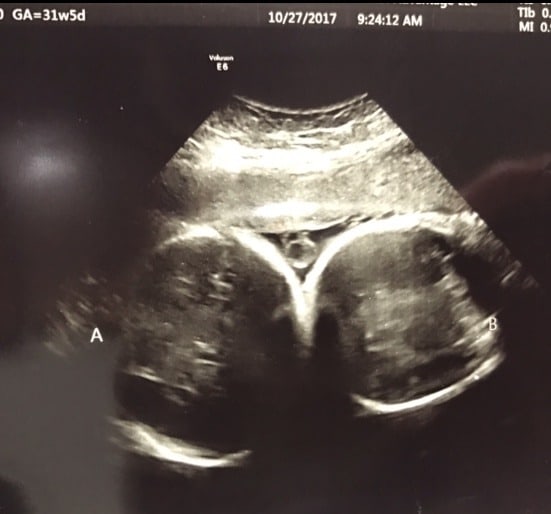

Ultrasound photos at 31 weeks pregnant with twins